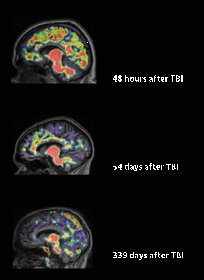

The Latest Research on Traumatic Brain Injury (#TBI): Causes, Diagnostics, Treatments

While waiting at my neurologist’s office for my second appointment (at which I was cleared to return to regular activities, unrestricted, like WRITING MY BOOKS! YIPPEE!), I read a fascinating article, “Tracking Traumatic Brain Injury: What New Biomarkers May Reveal About Concussion Over the Short and Long Term,” by Gina Shaw, about the latest and greatest advances in Traumatic Brain Injury (#TBI).

Having suffered a “mild-to-moderate” #concussion myself on April 6, I have a keen interest in all of these topics.

The links and website for the article and magazine are below. First, my favorite parts are summarized or quoted, here. [There were no images with the article, so I went and found some (Thanks to Google images!).]

1. “Despite years of research into traumatic brain injury (TBI), the tests currently available to neurologists, emergency physicians, and other experts can’t reliably identify who has sustained a TBI after a blow to the head, and who has not.” [emphasis is mine]

2. “Damage to neurons occurring after a mild to moderate TBI–called axonal injury–is not revealed on these [CT] scans.” [emphasis is mine]

The image I found, below, is generated by one of the latest diagnostic tools, Diffuse Tensor Imaging, or DTI (see #6, below).

image from trialexhibitsinc.com, “Diffuse Axonal Injury (TBI)”

3. “‘Some studies indicate that having had even a “mild” TBI in early or midlife may increase the risk for dementia in late life, probably at least twofold.’” states Ramon Diaz-Arrastia, M.D., Ph.D., Fellow of the AAN [American Academy of Neurology], director of clinical research at the Center for Neuroscience and Regenerative Medicine at the uniformed services University of the Health Sciences in Bethesda, MD. [emphasis is mine]

4. Even a mild to moderate TBI causes an Axonal Injury = one that disrupts the brain’s structure and chemistry on a cellular level. [emphasis is mine]

image from http://www.alzforum.org, “Amyloid plaques in a cross-section of TBI patients.”

5. 2013 research shows that the same plaque (made of amyloid, a brain protein) that is distributed widely in the brains of and that causes dementia in Alzheimer’s Disease (AD) is found at the site of a TBI, even a mild one. Some researchers are using the anti-amyloid drugs given to AD patients on TBI injuries to avoid or lessen the likelihood of later dementia.

6. There is a new type of MRI called Diffusion Tensor Imaging (DTI) that is promising for seeing the neurological damage caused by TBIs in ways no other diagnostics are currently able to do. This will also aid in detecting where an injured person is in their recovery.

image from http://www.adlergiersch.com, “Advances in Neuroimaging in Detecting Brain Abnormality in ‘Mild’ Traumatic Brain Injury”

The article describes many other “in the field” (literally, athletic fields, for one) diagnostic tools about to become widely available to determine the extent or presence of a TBI in someone who was knocked on the head.